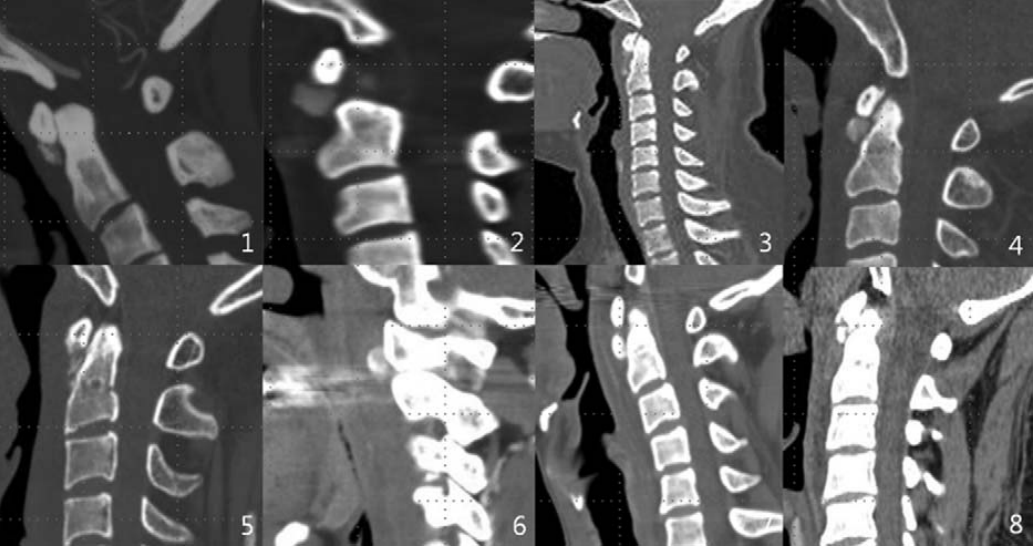

图:C2-3儿童颈椎间盘钙化合并后纵韧带骨化虽然本病可以发生在从新生儿到青春期, 但其发病高峰为6~10岁,男性多于女性,发病部位以颈椎间盘最为多见,胸椎次之,腰椎最少,颈椎中以C6-7和C3-4节段最为常见。一般为单一节段的椎间盘钙化,少数病例也可有两个部位的椎间盘钙化,部分病例可伴有后纵韧带骨化。另外,部分病例可出现神经刺激症状,且在影像检查中不仅可以看到椎间盘异常征象,还可显示肿块侵入椎管,甚至压迫脊髓,特别是合并后纵韧带骨化的病例,椎管侵占率往往大于50%。

图:患者8岁,女孩,因严重颈部疼痛、活动受限伴左上肢无力、麻木不适2天就诊。既往有锁骨骨折、额部软组织挫伤病史。查体:颈椎活动受限,左上肢肌力正常,但感觉减退。白细胞、血沉、CRP升高。颈椎侧位片和CT平扫提示C6-7椎间盘钙化(粗箭头)和后纵韧带骨化(细箭头),颈椎MRI提示C6-7水平脊髓明显受压。给予颈椎制动、枕颌带2.5kg颈椎牵引2周。随后,颈托固定1个月。2年后随访复查颈椎CT如下图,同时上述症状完全缓解。

图:2年后复查CT示C6-7钙化的椎间盘和后纵韧带骨化都消失了

图:8岁女孩,因颈腰痛伴左上肢放射痛2月余就诊,颈椎侧位片、CT和MRI表现与上述病例类似。

图:给予保守对症治疗(具体不详)1月后症状消失。6个月时随访可见钙化的椎间盘和后纵韧带都消失了。

图:6岁男孩,因颈痛就诊

图:保守治疗1个月后,症状消失。19个月随访情况

图:9年后随访情况

图:11岁女孩,因颈痛3月,加重半月就诊

图:经卧床休息、非甾体抗炎药、牵引2周和颈托固定2周后症状完全缓解。2月后复查情况

图:6个月复查情况参考文献:1. World Neurosurg. (2019) 129:181-185.2. Pediatric Neurology 61 (2016) e115-e1163. BMC Musculoskeletal Disorders (2018)19:3164. Childs Nerv Syst (2016) 32:381-3865. J Spinal Disord Tech 2012;25:59-636. 中华外科杂志,1996;34(4):197-200